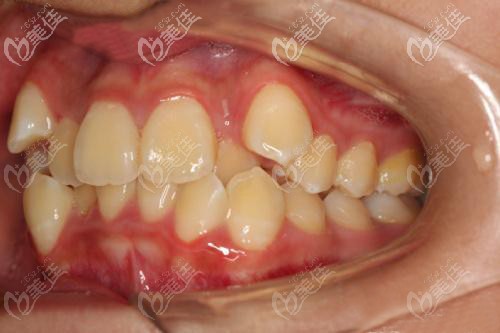

术前照片:

我本人是牙齿拥挤,一直想做矫正;所以,前两天到就到我们汉口比较有名的连锁牙科——牙达人口腔看看究竟做牙齿矫正怎么样!下面是我偶遇到一位17岁小妹妹牙列拥挤,戴金属自锁矫正器14个月的真实案例,分享给大家。

为何17岁就要戴牙套矫正牙齿拥挤:

牙列拥挤还导致了牙齿聚结、重叠和扭曲,长得乱七八糟。不仅仅是难看,而且刷牙和使用牙线都清理不干净牙缝的残留物;时间一长,还出现了蛀牙~